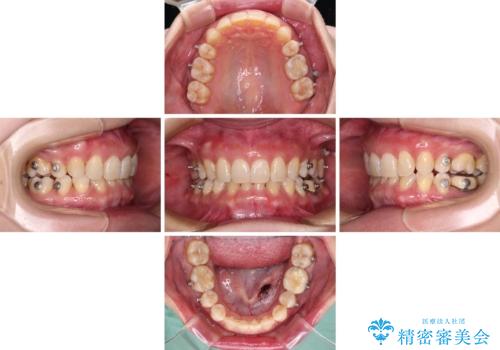

下顎2前歯の欠損 インビザラインによる抜歯矯正

- 下顎前歯欠損による歯列不正を気にして来院された患者様です。

下顎の歯列が小さく、下顎前歯が隠れてしまう過蓋咬合(ディープバイト)であったため、

マウスピースでの抜歯矯正特有の抜歯スペースに向かって奥歯が傾斜する動きが顕著に表れ、ディープバイトは改善されませんでした。

前歯のみが強く接触し、奥歯で咬めない期間も続いたため、ワイヤー装置などを補助的に使用し、何とか終了させることができました。